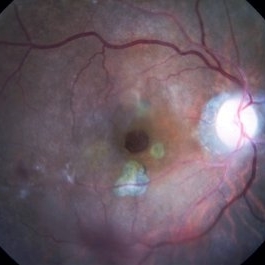

Myopic Degeneration, Macular Hemorrhage

Sep 10 2014 by Mehul A Shah

A 50-year-old male patient presented with complaint of sudden loss of vision.

Photographer: Drashti Netralaya,Dahod

Imaging device: FF 450

Condition/keywords: myopic degeneration